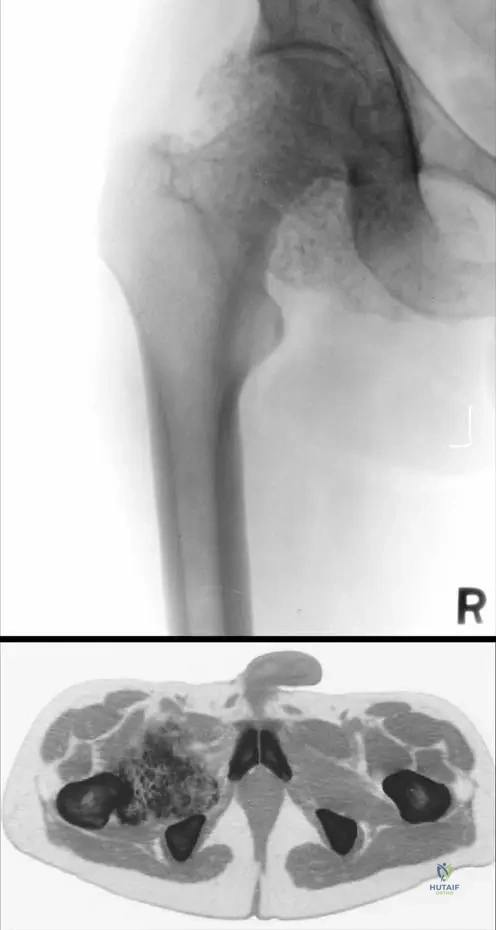

A 40-year-old male presents with chronic right hip pain and mechanical symptoms. A CT scan of the hip is provided. Based on the image and clinical context, what is the most prominent feature observed?

View Answer & Explanation

Correct Answer: C

Rationale: The clinical context for Fig. 10.1 a, b explicitly states: "Note the enlarged joint capsule filled by large mass of intra-articular calcified cartilaginous free bodies." This is clearly visible on the CT scan (b). Avascular necrosis, labral tears, insufficiency fractures, and periosteal reactions are not the primary features highlighted in the image or text for synovial chondromatosis.

A 44-year-old male presents with chronic right hip pain and limited mobility. Plain radiographs of the hip are obtained. Based on the image, what is a key radiographic finding indicative of synovial chondromatosis?

Rationale: The clinical context for Fig. 10.1 a, b explicitly states: "Note the enlarged joint capsule filled by large mass of intra-articular calcified cartilaginous free bodies." This is clearly visible on the plain radiograph (a). Widening of the joint space is not typical. Significant osteophyte formation and subchondral lucencies can be seen in osteoarthritis, which can be secondary, but the primary finding for synovial chondromatosis is the calcified bodies within an enlarged capsule. Bone marrow edema is a finding on MRI, not plain radiographs.

A 45-year-old male presents with chronic, progressive pain and stiffness in his right hip. He reports intermittent locking and catching sensations. Radiographs show multiple intra-articular calcified bodies and an enlarged joint capsule. A CT scan confirms a large mass of intra-articular calcified cartilaginous free bodies filling the joint capsule.

Rationale: The clinical presentation of chronic pain, stiffness, mechanical symptoms (locking/catching), and radiographic findings of multiple intra-articular calcified cartilaginous free bodies within an enlarged joint capsule are classic for synovial chondromatosis. This condition is characterized by a benign proliferation of cartilaginous tissue in the synovium that can detach and form loose bodies. Osteochondroma is a bone tumor with a cartilaginous cap, typically exophytic from bone, not intra-articular loose bodies. Pigmented villonodular synovitis presents with hemosiderin deposition and often causes effusions and erosions but typically does not produce calcified cartilaginous loose bodies. Chondrosarcoma is a malignant tumor and while it involves cartilage, its presentation and radiographic features differ significantly from the benign, multifocal loose bodies of synovial chondromatosis. Gouty arthritis involves uric acid crystal deposition and presents with acute inflammatory episodes, not calcified cartilaginous loose bodies.